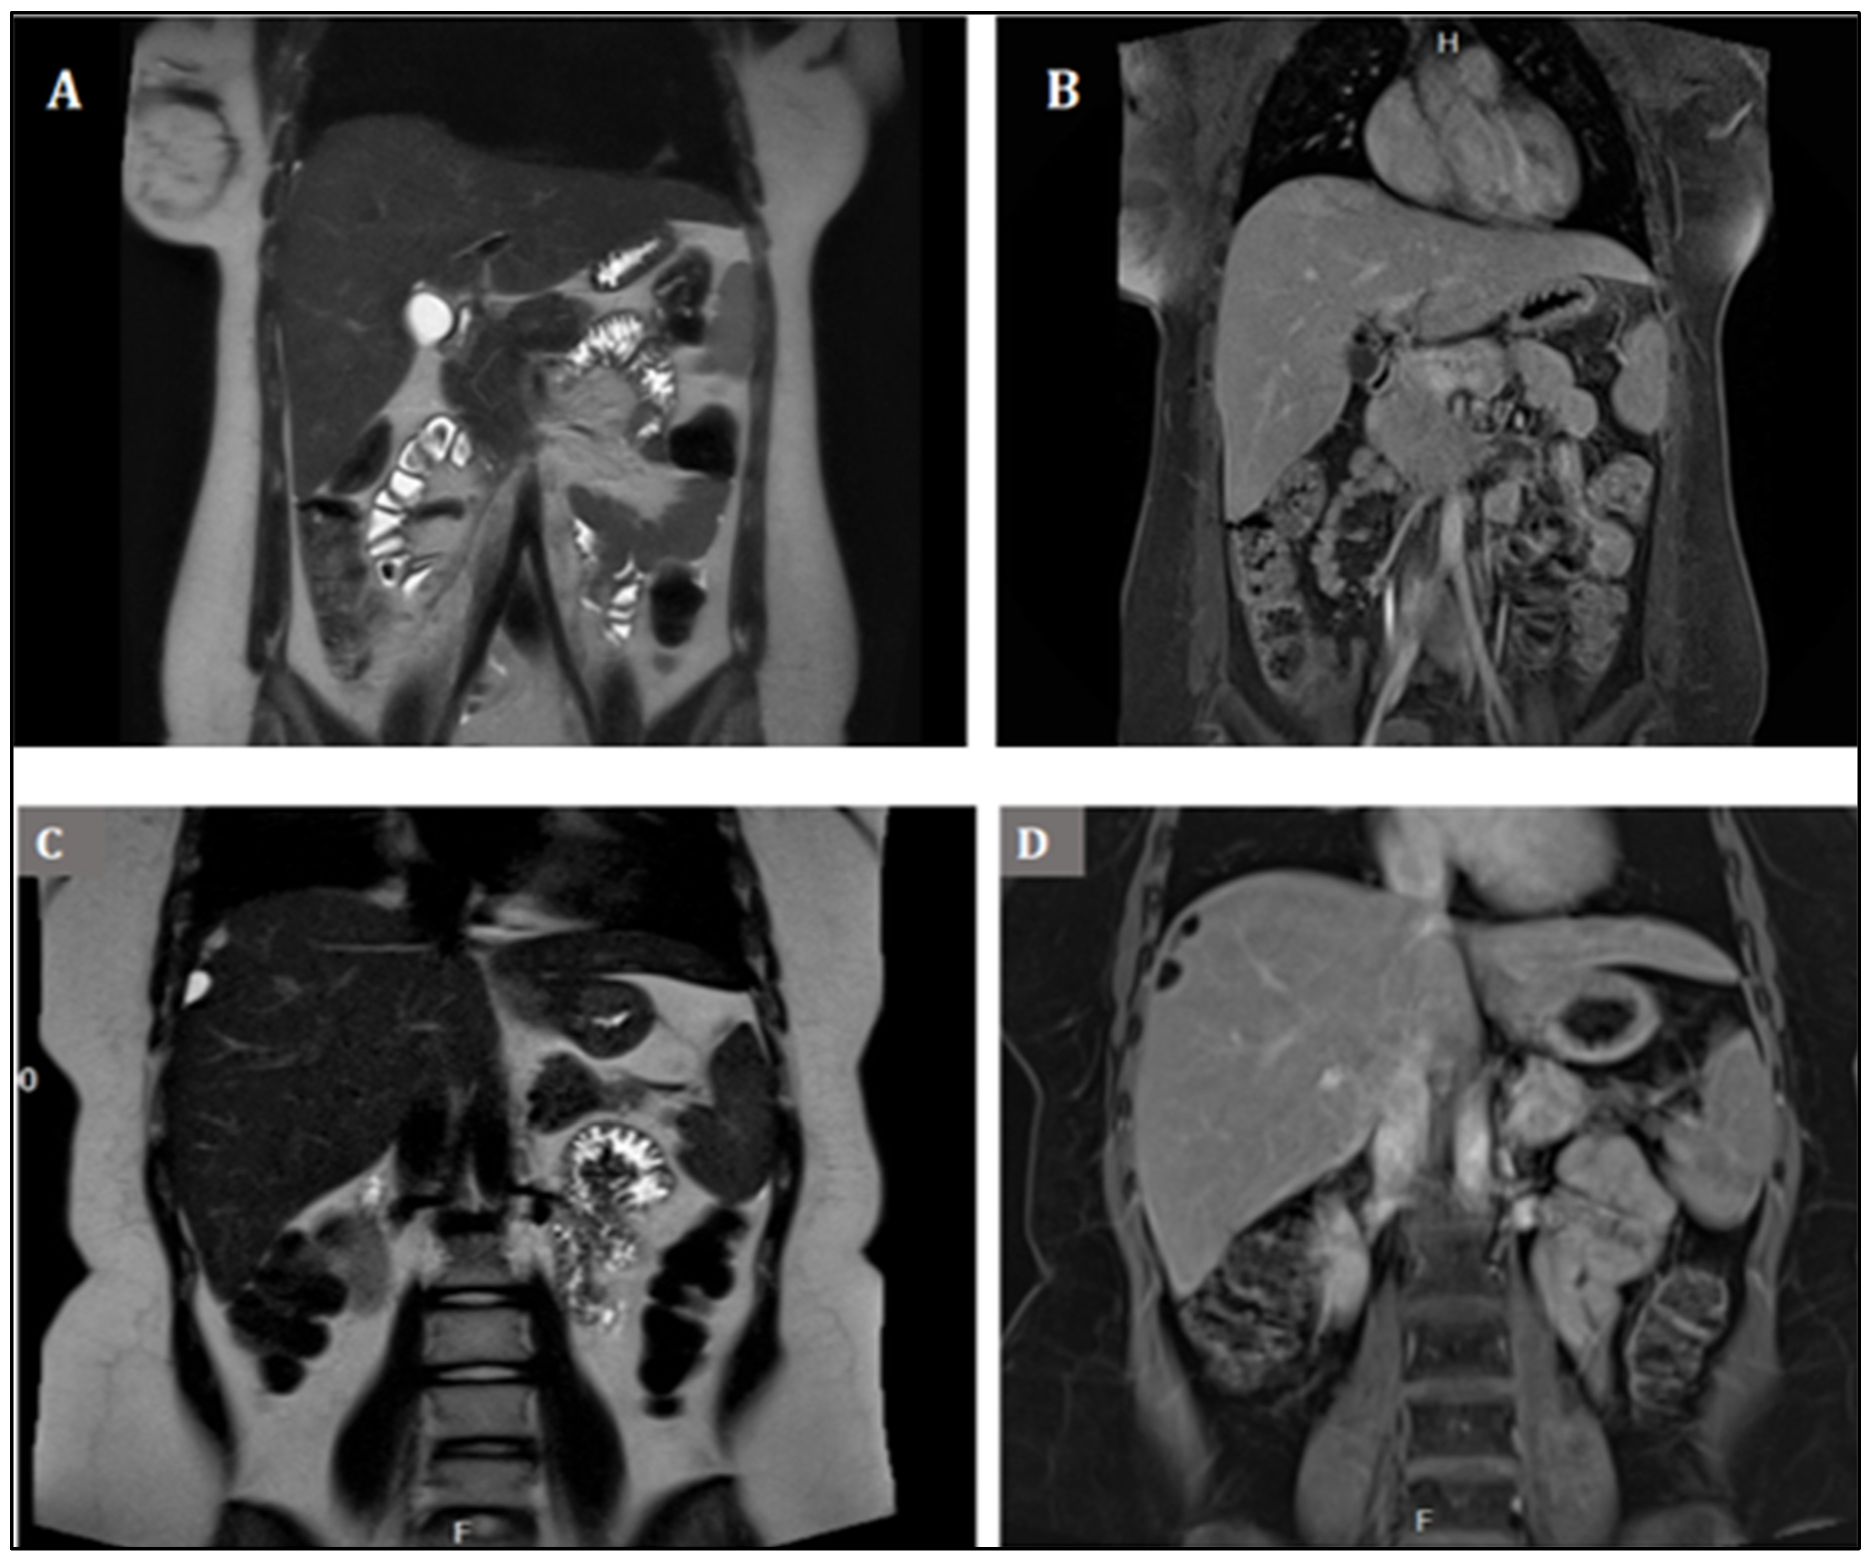

2. Case Presentation